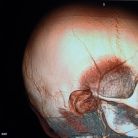

Ultrarzadka operacja w szpitalu dziecięcym w Olsztynie (fot. archiw. WSSD) | Więcej zdjęć »

W Wojewódzkim Specjalistycznym Szpitalu Dziecięcym w Olsztynie wykonano skomplikowany zabieg mikronaczyniowy u 3-letniego chłopca z zespołem moyamoya i neurofibromatozą typu I.

Zespół Kliniki Chirurgii Głowy i Szyi Dzieci i Młodzieży WSSD w Olsztynie we wtorek (30.07) przeprowadził zabieg mikronaczyniowy w obrębie ośrodkowego układu nerwowego u 3-letniego pacjenta. Chłopiec choruje na chorobę rzadką zwaną neurofibromatozą typu 1. Choroba ta dotyka jedynie 1 na 2500-3500 ludzi. W niezwykle rzadkich przypadkach (u ok.0,6% pacjentów z neurofibromatozą typu 1) pojawiają się objawy tzw. zespołu moyamoya. W Polsce jak dotąd było operowanych jedynie kilka dzieci z zespołem moyamoya - pacjent WSSD w Olsztynie jest najprawdopodobniej najmłodszym dotąd dzieckiem z tym schorzeniem operowanym w Polsce.

- Zespół moyamoya polega na stopniowym zarastaniu światła tętnic szyjnych wewnętrznych, czyli dużych tętnic doprowadzających krew do przedniej i środkowej części mózgowia - mówi dr n. med. Patrycja Larysz, specjalista neurochirurgii. - Ten postępujący proces chorobowy najczęściej skutkuje udarami mózgu, padaczką oraz zaburzeniami rozwoju dziecka. Zabieg polegał na połączeniu krążenia zewnątrzczaszkowego z krążeniem wewnątrzczaszkowym. Leczenie takich dzieci wymaga interdyscyplinarnej diagnostyki radiologicznej, onkologicznej oraz neurologicznej i neurochirurgicznej.

- Zabieg wymagał zastosowania metod mikroneurochirurgii naczyniowej, śródoperacyjnej ultrasonografii dopplerowskiej oraz wideoangiografii zielenią indocyjaniny z cyfrową analizą przepływów naczyniowych - dodaje prof. Dawid Larysz, Kierownik Kliniki Chirurgii Głowy i Szyi Dzieci i Młodzieży WSSD w Olsztynie.